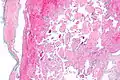

Intravascular papillary endothelial hyperplasia is a rare, benign tumor. It may mimic an angiosarcoma, with lesions that are red or purplish 5-mm to 5-cm papules and deep nodules on the head, neck, or upper extremities.[1][2]: 592

Histopathology Images